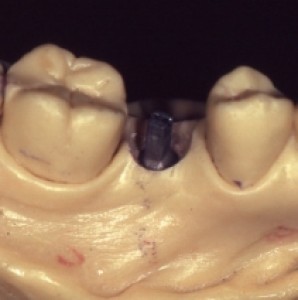

Obiettivi. Lo scopo di questo articolo è descrivere una serie di tecniche utili a migliorare l'estetica delle riabilitazioni implantari nel mascellare anteriore.Materiali e metodi. Si descrive...